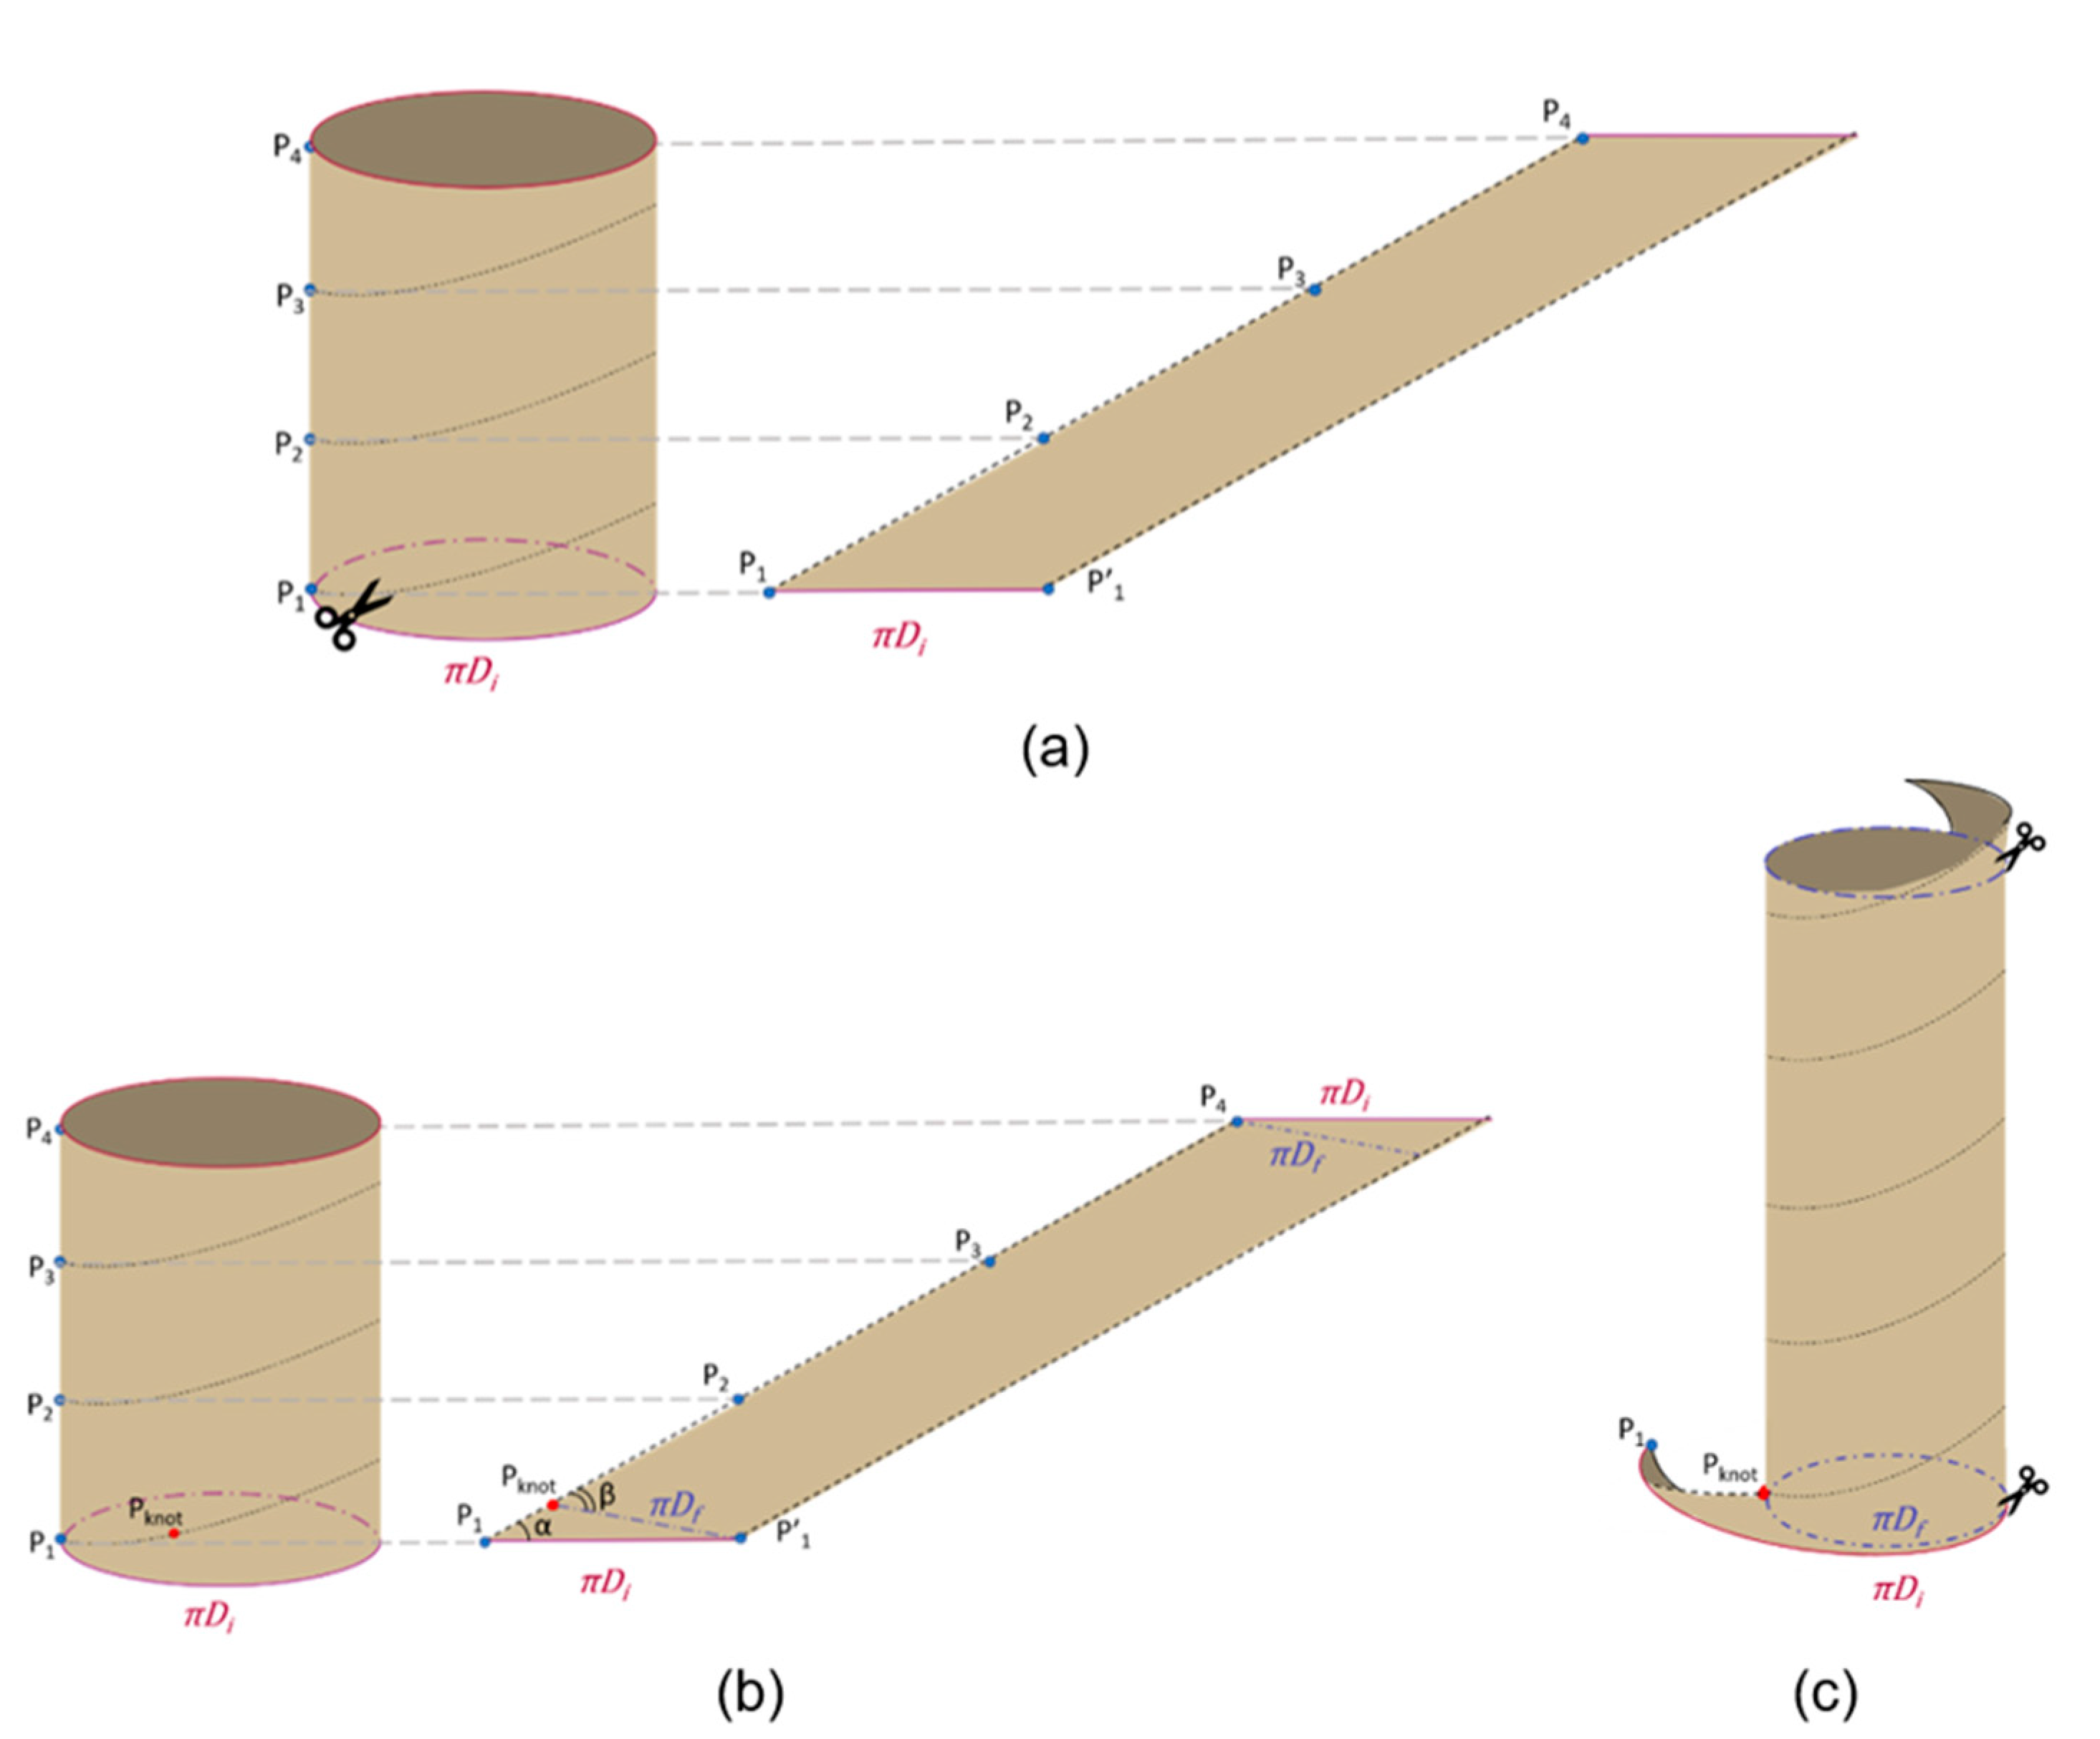

2.1. The Geometry of the SILT Procedure